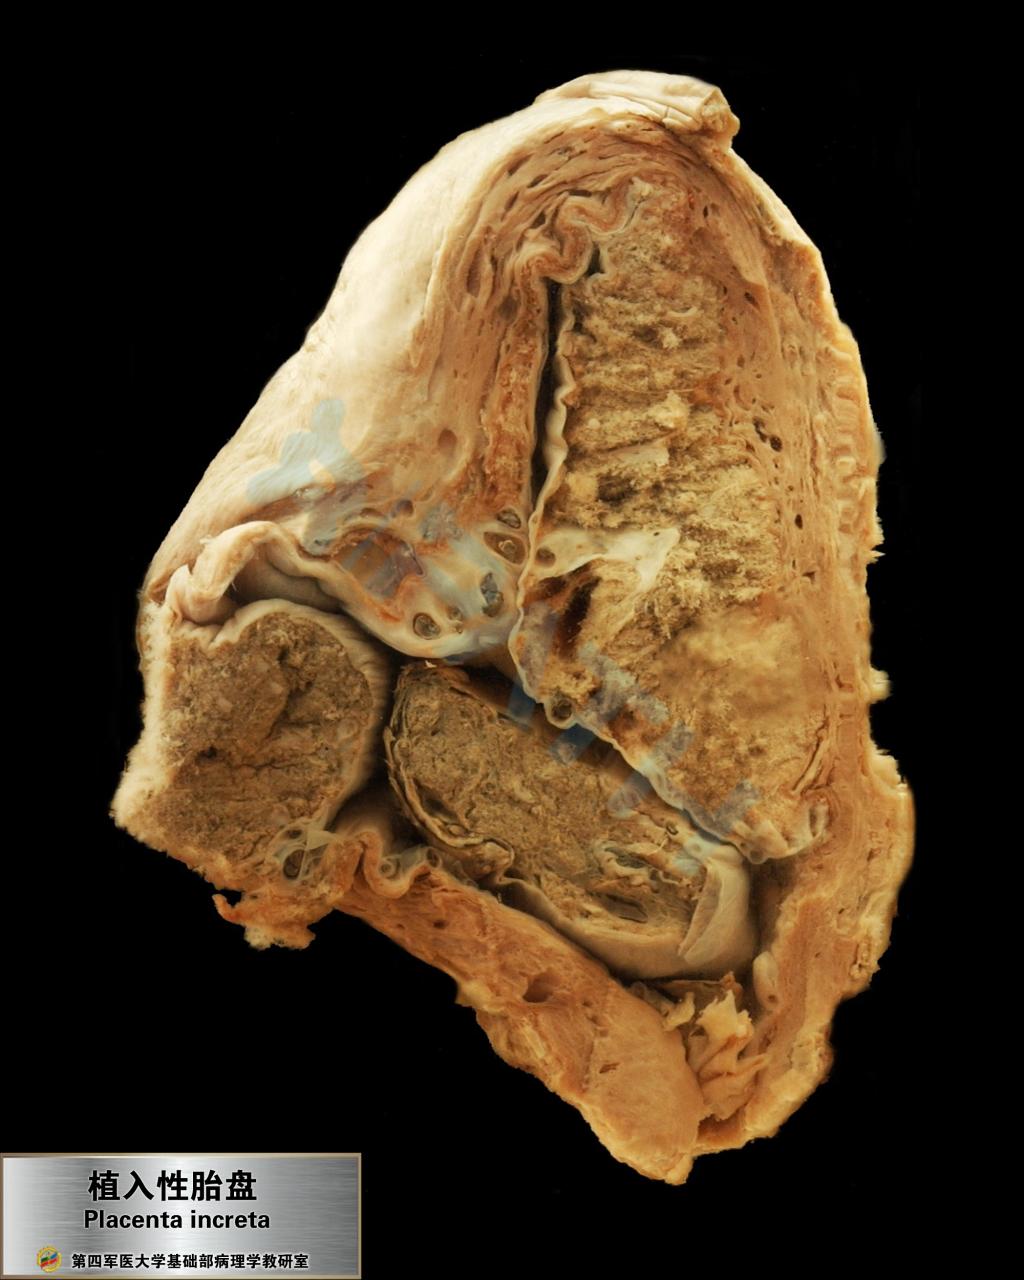

植入性胎盘